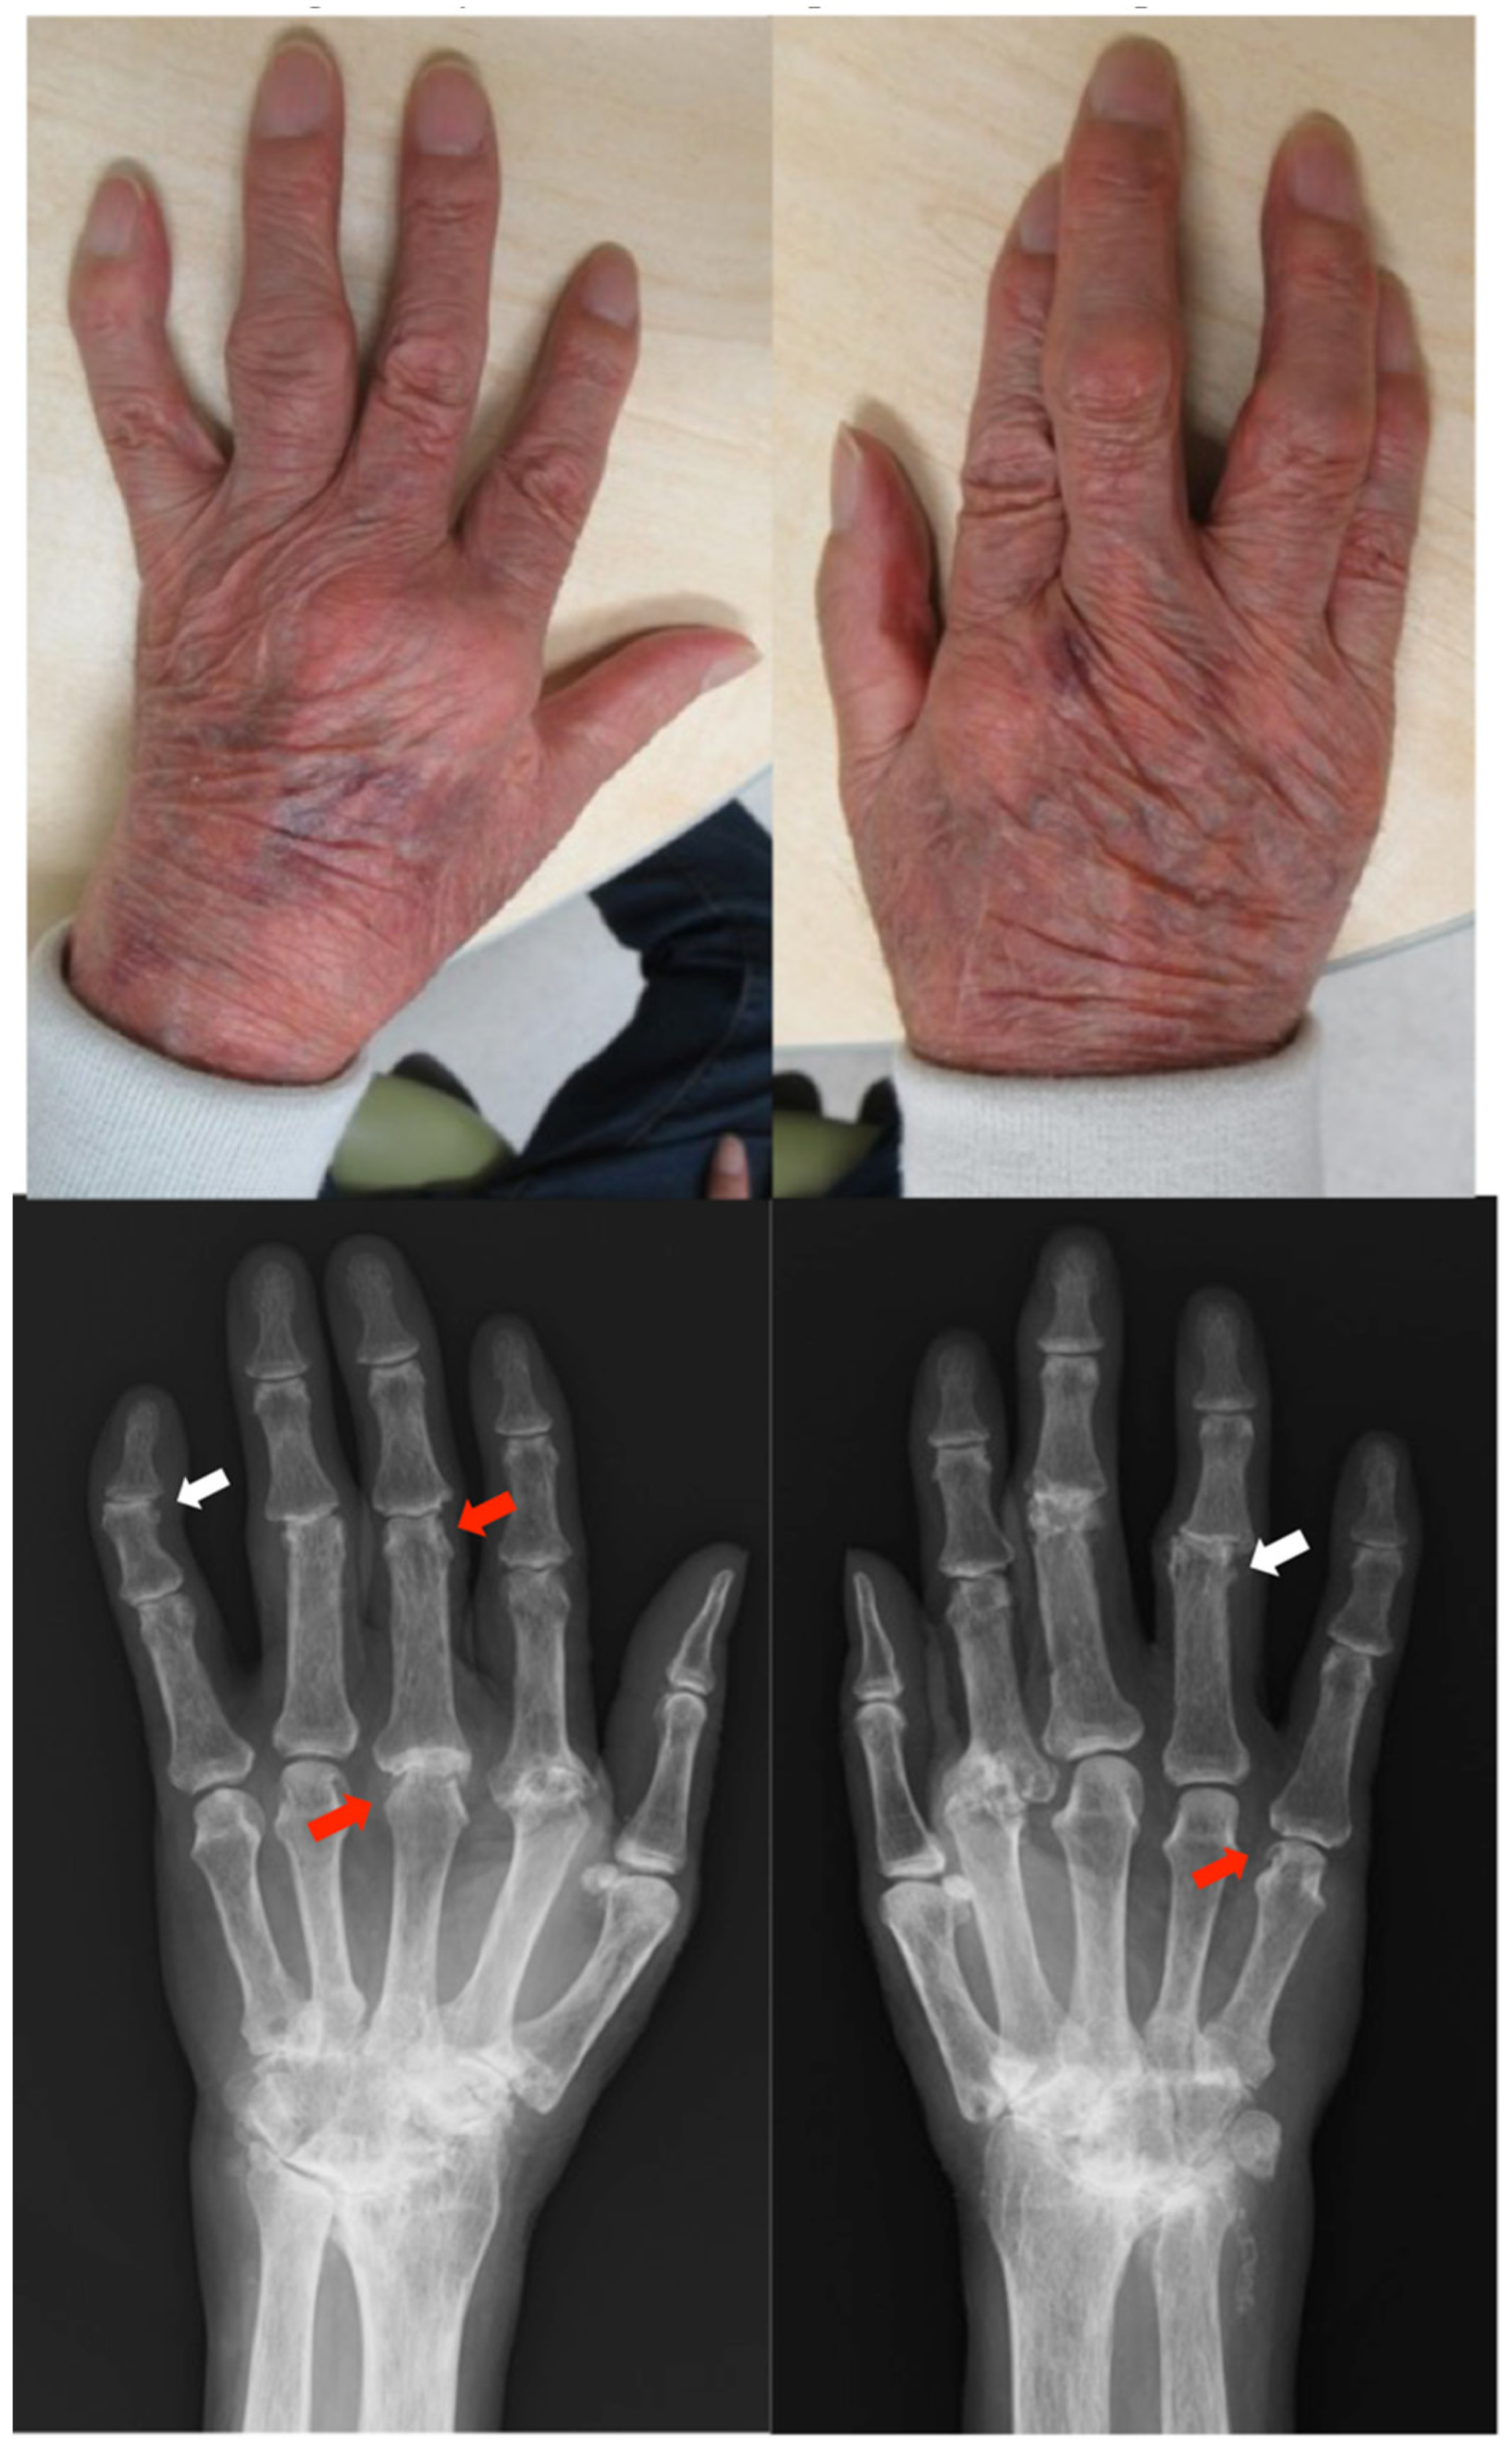

Patient: Man in his 70s

Patient: Man in his 60s